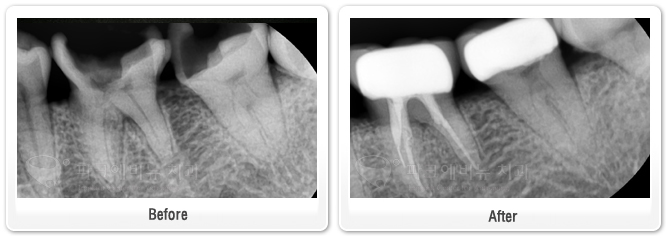

파크에비뉴치과 충치 수면마취, 수면신경치료 전 후 비교

#36,37- 왼쪽 아래 첫 번 째 큰 어금니는 충치 균이 신경까지 침투하여 수면신경치료를 시행하였고 두 번 째 큰 어금니는 다행히 신경이 손상 되지 않아 치아를 보강한 뒤 크라운으로 씌워주었다.